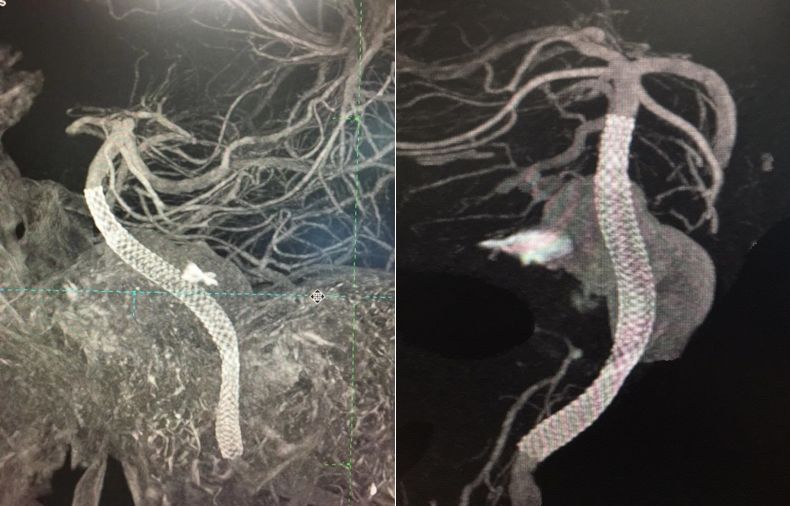

术后造影显示PED完全覆盖动脉瘤,载瘤动脉通畅。术后DynaCT 显示支架位置及打开良好。

PED支架顺利释放,与原支架顺利桥接重叠。术后即刻造影显示PED位置满意,动脉瘤内可见造影剂滞留。

DynaCT显示两枚支架形态良好。

术后1个月复查头颅CTA显示支架位置良好,左侧椎动脉与基底动脉汇合处闭塞,左侧小脑后下动脉动脉瘤仍显影。

2. 本例再次送入一枚PED,术中有意识地把第二枚支架的远心端尽量靠近基底动脉顶部打开,在正常载瘤动脉内应用推送技术,两枚支架完美桥接并部分套叠,增加了支架径向支撑力,并且有助于支架远端锚定,从而增加了支架的稳定性。